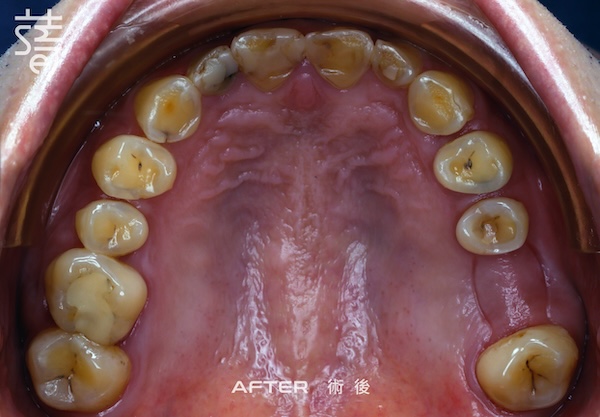

最後進行全口假牙與美學修復。許多人以為這一步只是追求美觀,其實這正是確保牙齒能長期穩定的關鍵步驟,讓美觀與功能同時回歸理想。

Finally, full-mouth prosthetics and aesthetic restoration were completed. Many assume this step is purely cosmetic, but it’s actually crucial for long-term stability.

經過一段完整而細緻的治療,李先生終於重新露出久違的笑容,自然、上鏡,也能自在享受每一口美食。

After a thorough and meticulous treatment, Mr. Li finally revealed a long-lost smile—natural, camera-ready, and able to enjoy every bite with ease.

從矯正、植牙、臨時假牙的調整,到最終假牙的完成,每一步都凝聚著薛醫師的專注與團隊的細心。透過 Modjaw 的動態咬合紀錄與國際專家的臨床經驗,蒔美讓李先生的笑容不只漂亮,更兼具穩定與健康。

From alignment, implants, and temporary prosthetic adjustments to the final restoration, every step reflected Dr. Xue’s focus and the team’s care. With Modjaw’s dynamic bite records and international expertise, Smile ensured Mr. Li’s smile was not only beautiful but stable and healthy.